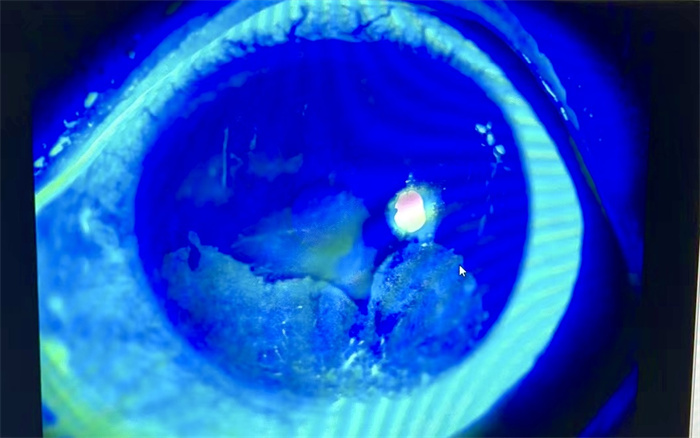

(502胶水粘附于角膜上并使角膜硬化 爱尔眼科医院供图)

小永表示左眼当场就被粘住了,并且伴有刺痛感。由于502的黏性很强,滴入眼睛后,小永眼睑周围的皮肤和睫毛都黏连在一起,眼睛无法睁开。情急之下,小永就近来到了泉州爱尔眼科医院急诊。泉州爱尔眼科医院值班医生吴少娟立即为小永开通绿色通道,检查后发现小永左眼的眼皮、睫毛都被胶水粘住了导致眼睛睁不开。吴少娟医生当即便为小永处理患眼,使用大量生理盐水冲洗后,小心翼翼的沿着睫毛根部将睫毛剪断,才打开小永的眼睑,使其睁开眼睛以进行接下来的检查。经过专业的眼科设备检查,吴少娟医生诊断其为左眼眼睑异物、角膜异物、角膜上皮损伤,需通过清除附着在角膜上的502胶水,带上绷带镜以保护角膜、缓解疼痛,同时应使用对症的消炎、抗感染的眼药水。